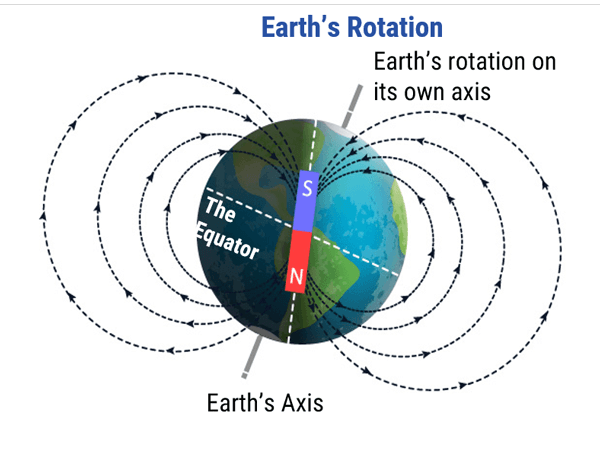

The imaging in MRI involves the very small magnetic force created by spinning protons within the nucleus of atoms. Protons are dipoles, much like the earth, with a north and South Pole and they spin or rotate on an axis. All dipoles process, or spin, at a unique frequency. This means that every proton has its own frequency at which it spins. This basic knowledge led to quite a realization about magnetic fields and signal given off by these magnetic fields under certain conditions, which we will learn more about as we progress. For now, it’s sufficient to say that this is the basis for what we know about MRI and how it works.

Before we go any further in that discussion, we need to understand a little more about the magnetic field. You may recall in grade school or later, playing with magnets in science class. These magnets would have been many millions of times LESS powerful than the magnet used in MRI. However, they all work with the same regardless of the strength. It is all the same physics concepts. This basic idea with magnetization is really the basis of MRI imaging. Let’s learn more about the magnetic field in MRI.

A magnetic field is defined as a region around a magnetic material or a moving electric charge within which the force of magnetism acts. Magnetism is an attraction and repulsion of forces between objects. This magnetism is observed around the earth. The earth is a larger scale example of a spinning object, which is also a dipole (north and south pole). The magnetic field of the earth allows us to use a compass to determine direction. We can also observe a magnetic field around permanent magnets and coils fed by electrical charge.